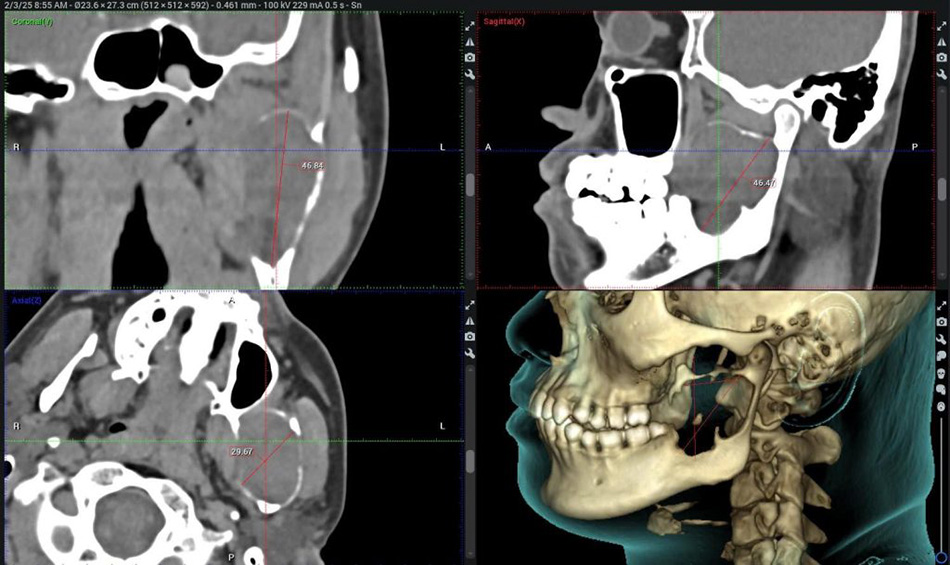

The Tumour, nearly 50 mm in size, caused jawbone destruction

Upon examining Mr C, and reviewing CBCT (Cone Beam Computed Tomography) imaging, Nguyen Thanh Tung, MD, PhD, Head of the Oral & Maxillofacial Surgery – Dental Surgery Department at FV Hospital, identified a cystic lesion that had almost completely destroyed the lower jawbone, extending from the angle of the jaw up to the condyle. “The patient’s wisdom tooth (number 38) was impacted and fused with the tumour, which could be one of the contributing factors to the formation of the tumour,” Dr Tung explained.

Fortunately, the tumour remained confined within the bone, and the patient showed no signs of numbness in the chin or lower lip, indicating that the inferior alveolar nerve was unaffected. Despite the tumour extending into the temporomandibular joint area, the patient maintained normal mouth opening. These findings suggested that conservative treatment was a viable option for the patient.

Post-treatment imaging shows tumour shrinkage and new bone formation